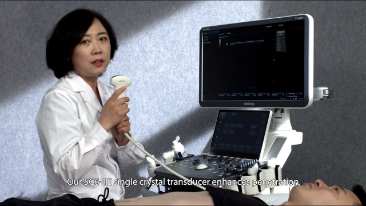

Desde que se fundó la compa?ía, Mindray ha explorado incansablemente nuevas formas de mejorar la confiabilidad del diagnóstico. Con la revolucionaria tecnología de ZONE Sonography?, la nueva plataforma ZST+ de Resona?7 lleva la calidad de la imagen por ecografía a un nivel superior mediante el procesamiento de datos de canal y la adquisición de zona.

Además de la calidad de imagen de primer nivel, Resona?7 también mejora las capacidades de investigación clínica con el revolucionario V?Flow para la evaluación hemodinámica vascular y con la adquisición de planos más inteligente a partir de conjuntos de datos 3D para el diagnóstico del SNC fetal. Al combinar el funcionamiento multitáctil basado en gestos más intuitivo y todas las características clínicas esenciales, Resona?7 realmente lidera las novedades en innovación de ecografías.